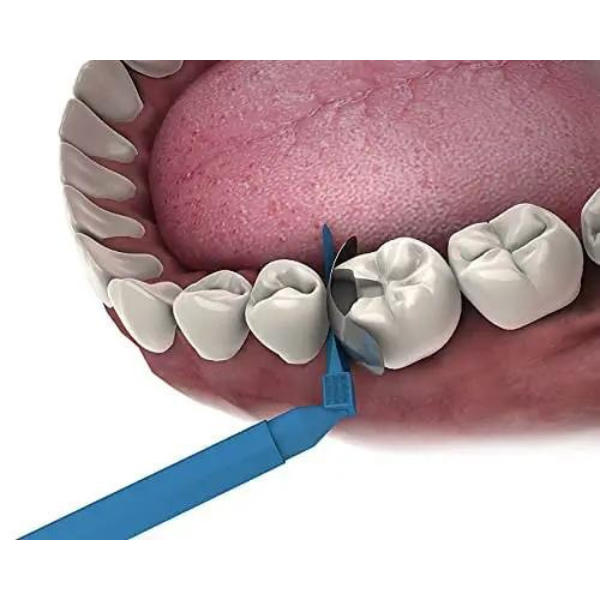

NMD NEXUS MEDODENT Automatrix Band With Metal (Orange Colours/Medium) (Pack Of 20 Pcs)

The Automatrix Band with Metal is a pre-assembled, retainerless matrix system designed to provide strong, stable support for Class II dental restorations. Made from high-quality stainless steel, this metal band offers excellent adaptability and ensures a tight, anatomical fit around the tooth structure—ideal for procedures requiring precise contour and contact.